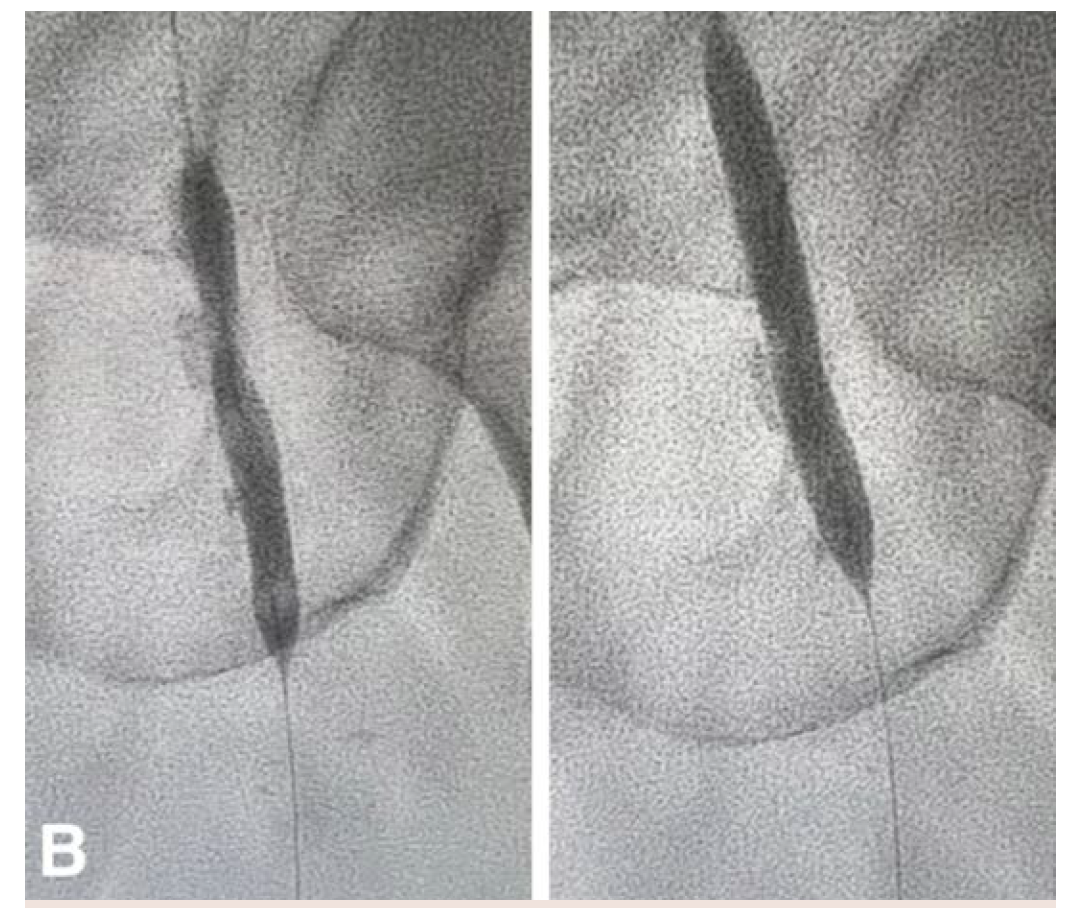

The patient underwent an initial catheter-directed diagnostic angiogram that revealed a 99% stenosis of the left CFA. The lesion was successfully transversed, and a 7 Fr 45-cm sheath was placed in the left external iliac artery. Intravascular ultrasound (IVUS) was performed over a 0.014" wire (Figure 1A), which demonstrated near occlusion of the CFA with heavy calcium burden. An 8-mm x 60-mm Shockwave balloon was then inflated to 4 atm, and 10 cycles were used to treat the CFA and proximal superficial femoral artery (Figure 1B). Completion angiogram showed an excellent result, with complete resolution of the calcific disease and no residual stenosis (Figure 1C). IVUS was performed at the end, which showed more than 80% luminal expansion after IVL treatment (Figure 1D). The patient was awakened from monitored anesthesia care and discharged from the postanesthesia care unit to home the same day.